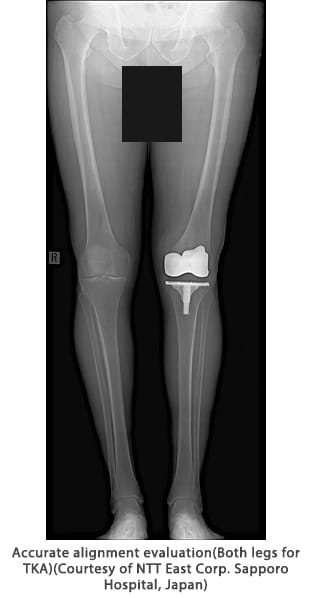

Long view imaging

This application provides simple operation, a large imaging area, and easy-to-interpret images for efficient examination and accurate diagnosis. It is available with the Shimadzu R/F system and general radiography systems.